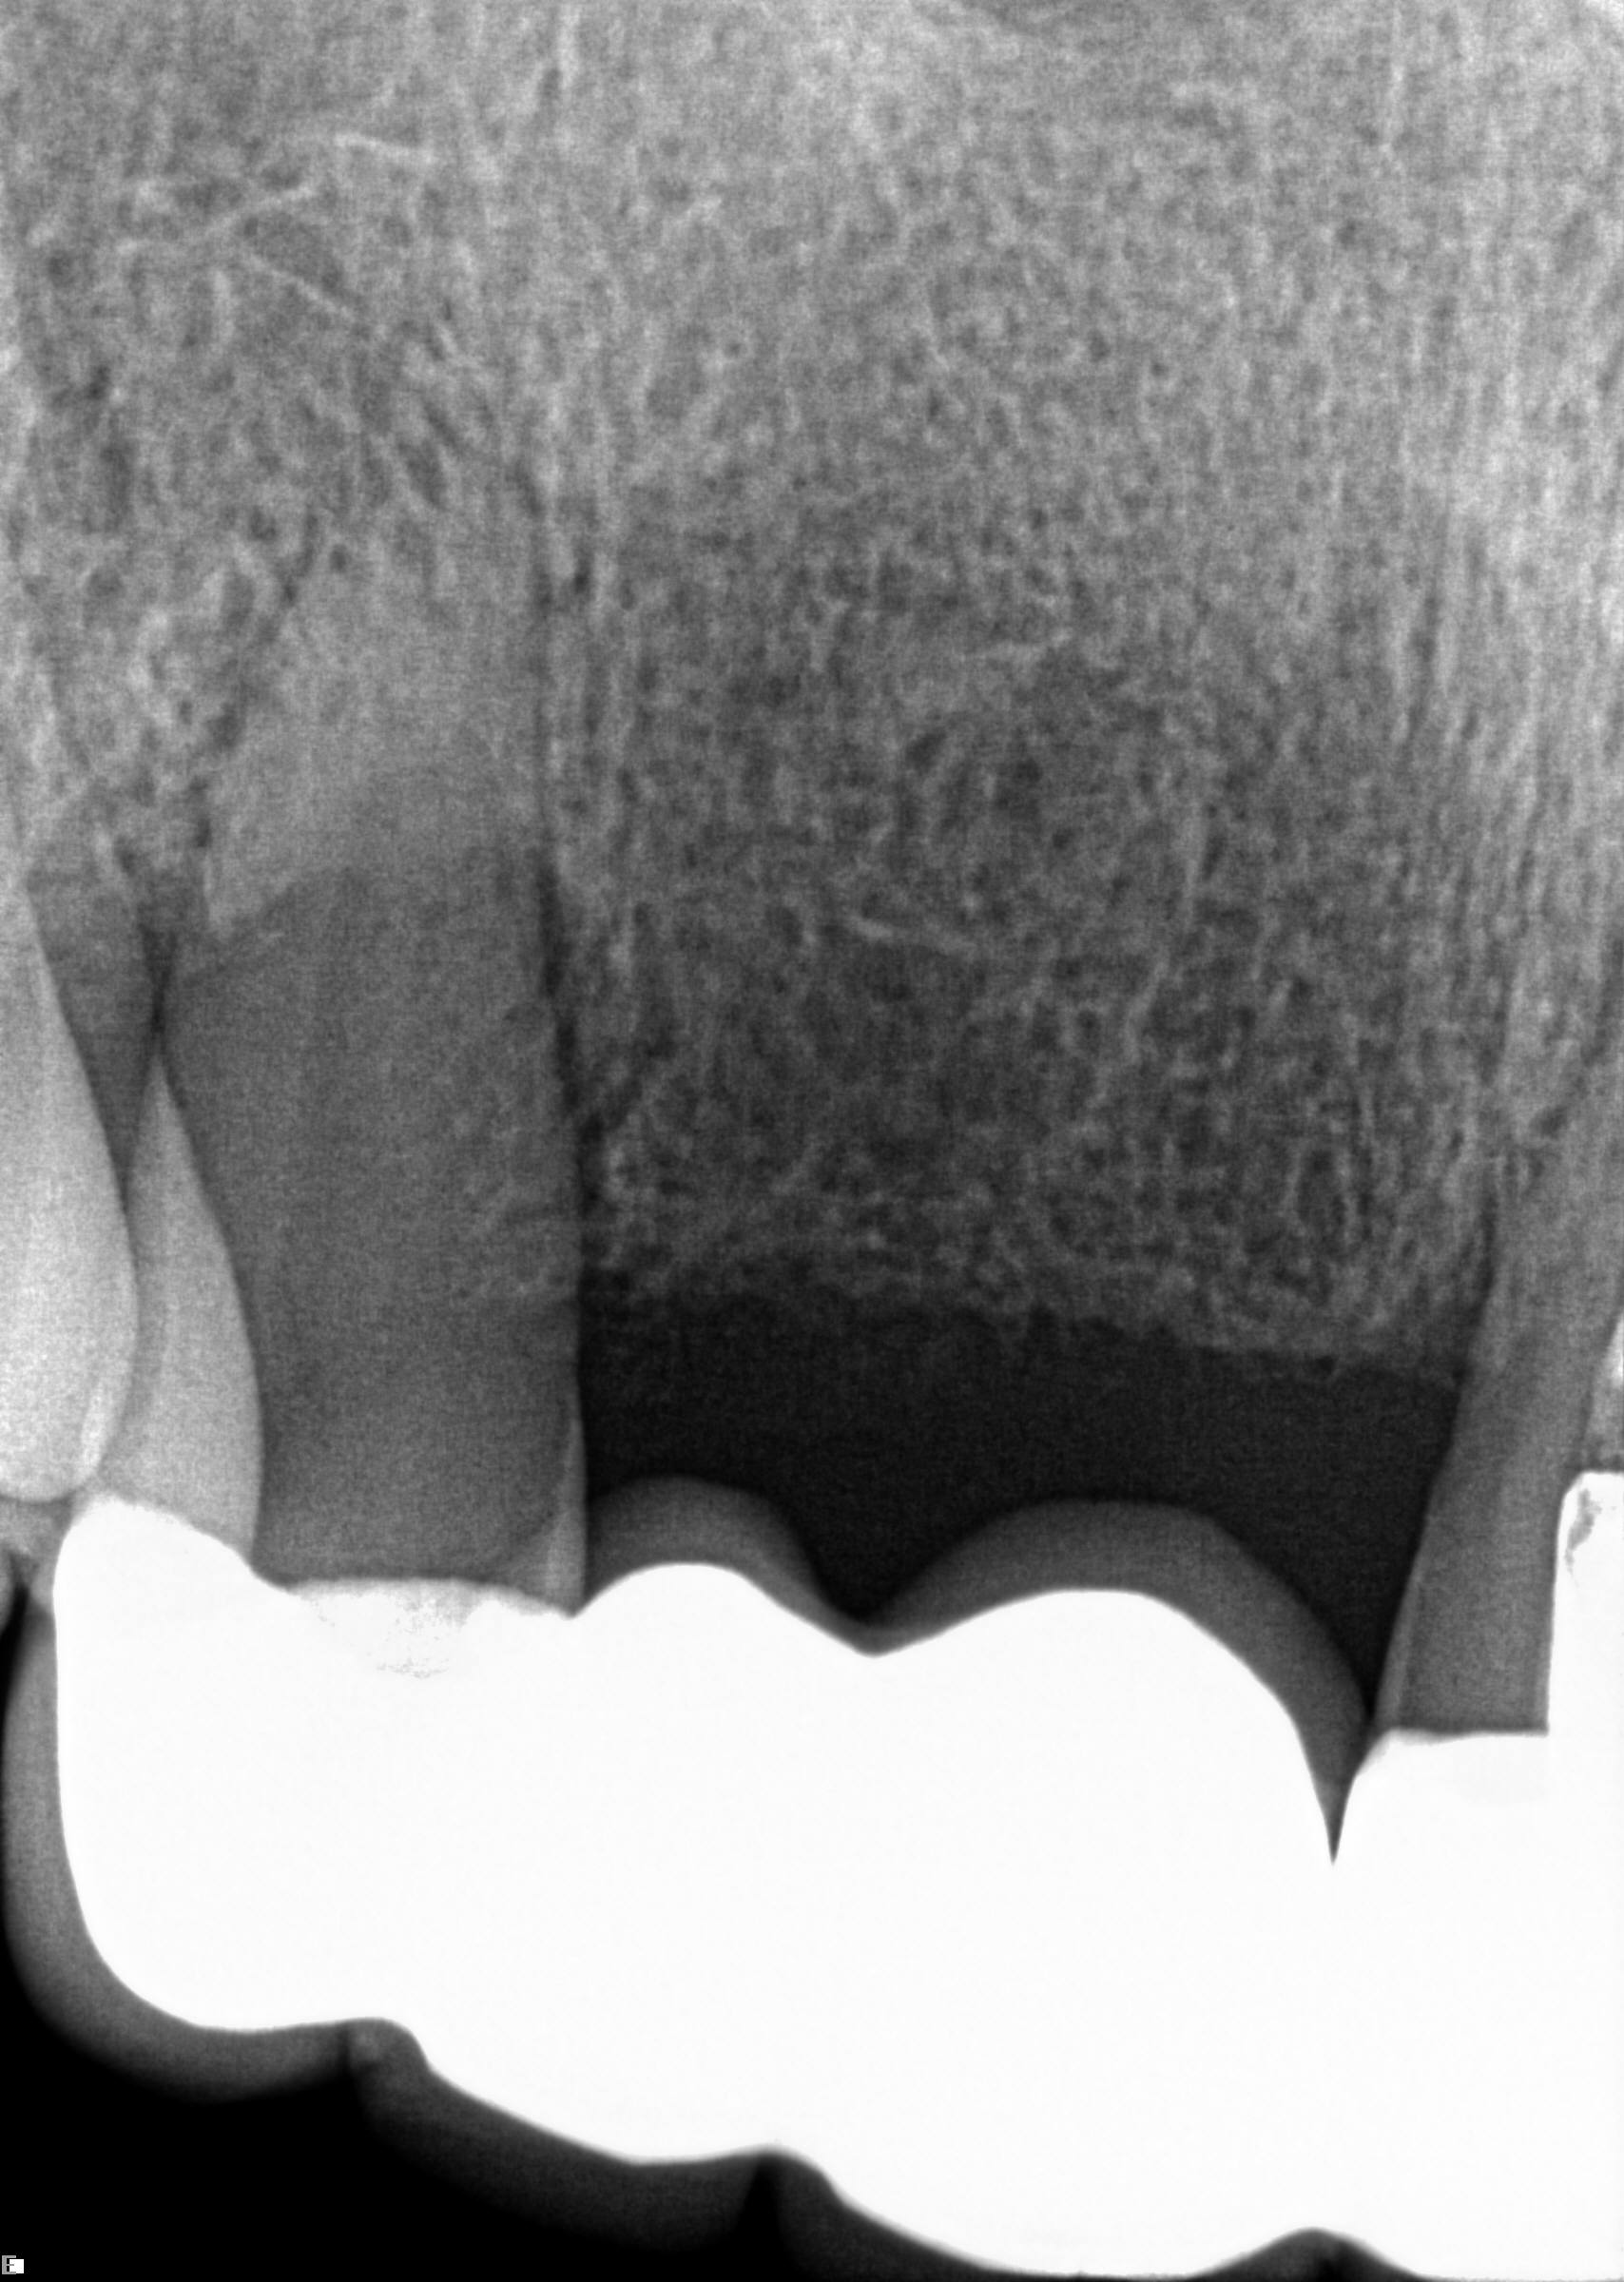

(1.) Case 1 initial radiograph of No. 19.

Figure 1

A 63-year-old woman presented with severe pain on biting of tooth No. 19 (Figure 1). Clinically there was pain on percussion and significant periodontal probing along the mesial root. The patient was anesthetized with infiltration anesthesia and the crown was horizontally sectioned from the lingual of the tooth. The remaining tooth was sectioned so the roots could be extracted individually. The socket was fully debrided and an implant was placed (Figure 2), which was prosthetically correct and stabilized in excess of 45 Ncm. The bone was milled to allow for unimpeded placement of a temporization abutment. The initial crown was revised to be the temporary crown in infraocclusion. Cement was extruded extraorally (Figure 3) prior to seating of the temporary restoration. The socket was sealed with the temporary crown and there were no sutures or bone graft (Figure 4 and Figure 5).